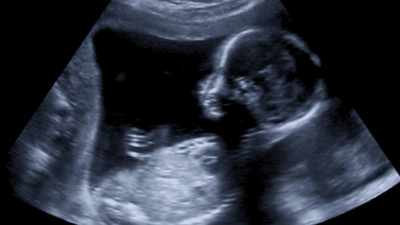

Kanada’nın başkenti Ottawa’daki Doğu Ontario Çocuk Hastanesi ve Ottawa Hastanesi'ndeki doktorlardan oluşan bir ekip, Sobia Bashir isimli annenin bebeğine, 2021 yılındaki doğum öncesi testlerde Pompe hastalığı teşhisi koydu.

Doktorlar, Pompe hastalarında eksik olan bir enzimi vermek için Ayla'nın annesine hamileliğinin 24. ve 37. haftaları arasında altı infüzyon verdi.

Bebekte eksik olan enzim, ultrason tarafından yönlendirilen iğneler kullanılarak fetal göbek kordonu damarına enjekte edildi.

Ottawa Hastanesindeki doğum öncesi enzim replasman tedavisinden sonra Ayla, 22 Haziran 2021'de dünyaya geldi.

Ayla’da yapılan testler, kalp ve kas gelişiminin normal olduğunu gösterdi.

Ayla bebek üzerinde gerçekleşen tedavi, dünya tıp literatürüne, "bir genetik hastalık için anne karnında tedavi edilen ilk bebek" olarak geçerken, vaka aynı zamanda "dünyanın ilk rahim içi tedavisi" olarak da tescillendi.